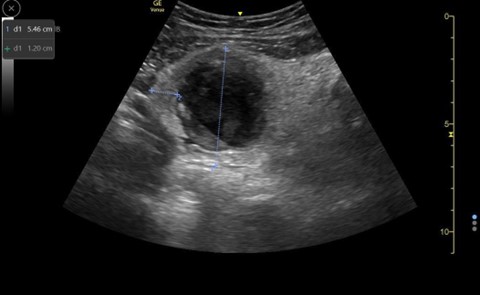

A 14-year-old female with a past medical history of anxiety and bipolar disorder presented to the emergency department with constant, sharp, non-radiating right lower quadrant abdominal pain. The pain began suddenly two nights ago and worsened with movement. She denied nausea, vomiting, diarrhea, fevers, or chills. On physical exam, her abdomen was tender to palpation in RLQ and RUQ with rebound and guarding. Labs demonstrated a leukocytosis of 12.9k with no other remarkable abnormalities. Given the broad differential of appendicitis vs ovarian torsion vs gallbladder disease, bedside ultrasound was performed. A non-compressible dilated appendix 7.3mm in diameter with an appendicolith present. (Image 1) Comprehensive radiology ultrasound of the abdomen demonstrated a non-peristalsing 6.5 x 1.1 x 1.6 cm tubular structure in the right lower quadrant concerning probable appendicitis. General surgery was consulted, and the patient underwent a laparoscopic appendectomy the same day. She underwent the procedure without complication and was discharged the following day.

Image 1. Image from case showing a dilated appendix suggestive of acute appendicitis with appendicolith and target sign present.

Image 7. Normal appendix, longitudinal view; appendix ending in blind pouch

When appendicitis is present, the appendix will measure greater than 6 mm from outer wall to outer wall, with a wall thickness greater than 3 mm and lack compressibility. (Images 1, 8, and 9) (Remember, you may want to do these measurements after you have obtained your images, given your patient a high five and a sticker, and stepped aside to perform measurements on the machine.) An inflamed appendix can demonstrate a “ring of fire” with enhanced color flow. Secondary findings you may see include: an appendicolith, (Image 1), periappendiceal free fluid (Image 10), a target sign (Image 1), enlarged mesenteric lymph nodes, thickening and hyperechogenicity of the overlying peritoneum (Image 8), dilated and hypoactive small bowel, and thickening of the apical cecal pole.